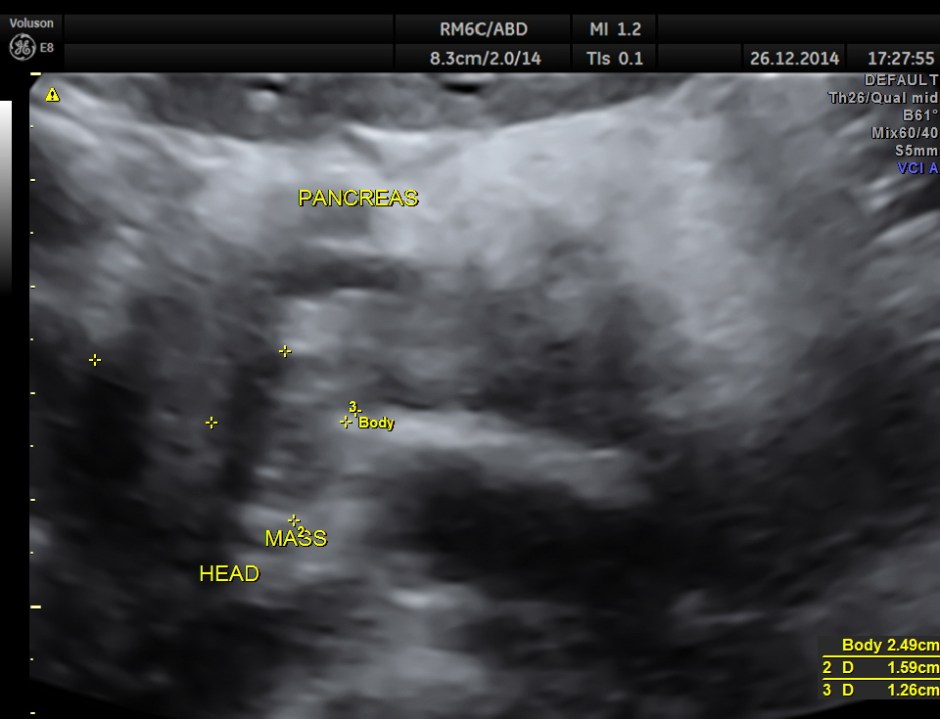

dilated pancreatic duct is seen

the head region of the pancreas shows an irregular mass lesion

volume contrast image – A plane image of the pancreas